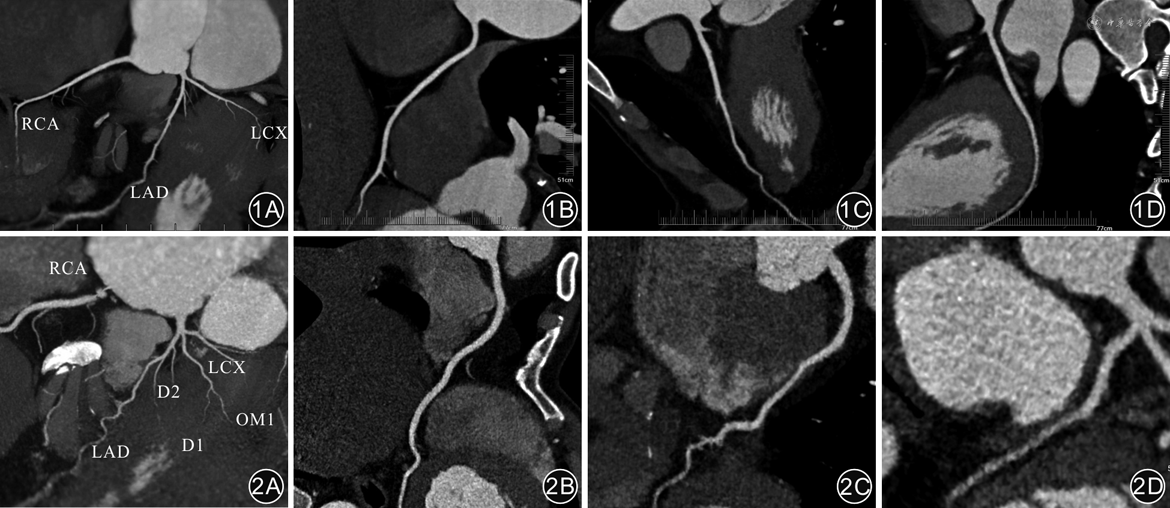

在对照组,3种不同模式CCTA扫描图像质量的冠状动脉分段法血管评分比较,差异无统计学意义(P>0.05),见表2、图1。在观察组,3种不同模式CCTA扫描图像质量的冠状动脉分段法血管评分比较,差异有统计学意义(P<0.001);A2组评分高于B2、C2组,差异均有统计学意义(P值均<0.05),见表2、图2。

注:RCA为右冠状动脉;LAD为左前降支;LCX为左回旋支;OM1为钝缘支;D1为第一对角支;D2为第二对角支

B1、C1组的左冠状动脉主干、各分支近段的CT值高于A1组,B2、C2组高于A2组,差异均有统计学意义(P值均<0.001),见表3。受检者主动脉根部的SNR值,左冠状动脉主干、各分支近段的CNR值,在A1、B1、C1 3组间比较,以及在A2、B2、C2 3组间比较,差异均无统计学意义(P值均>0.05),见表4。